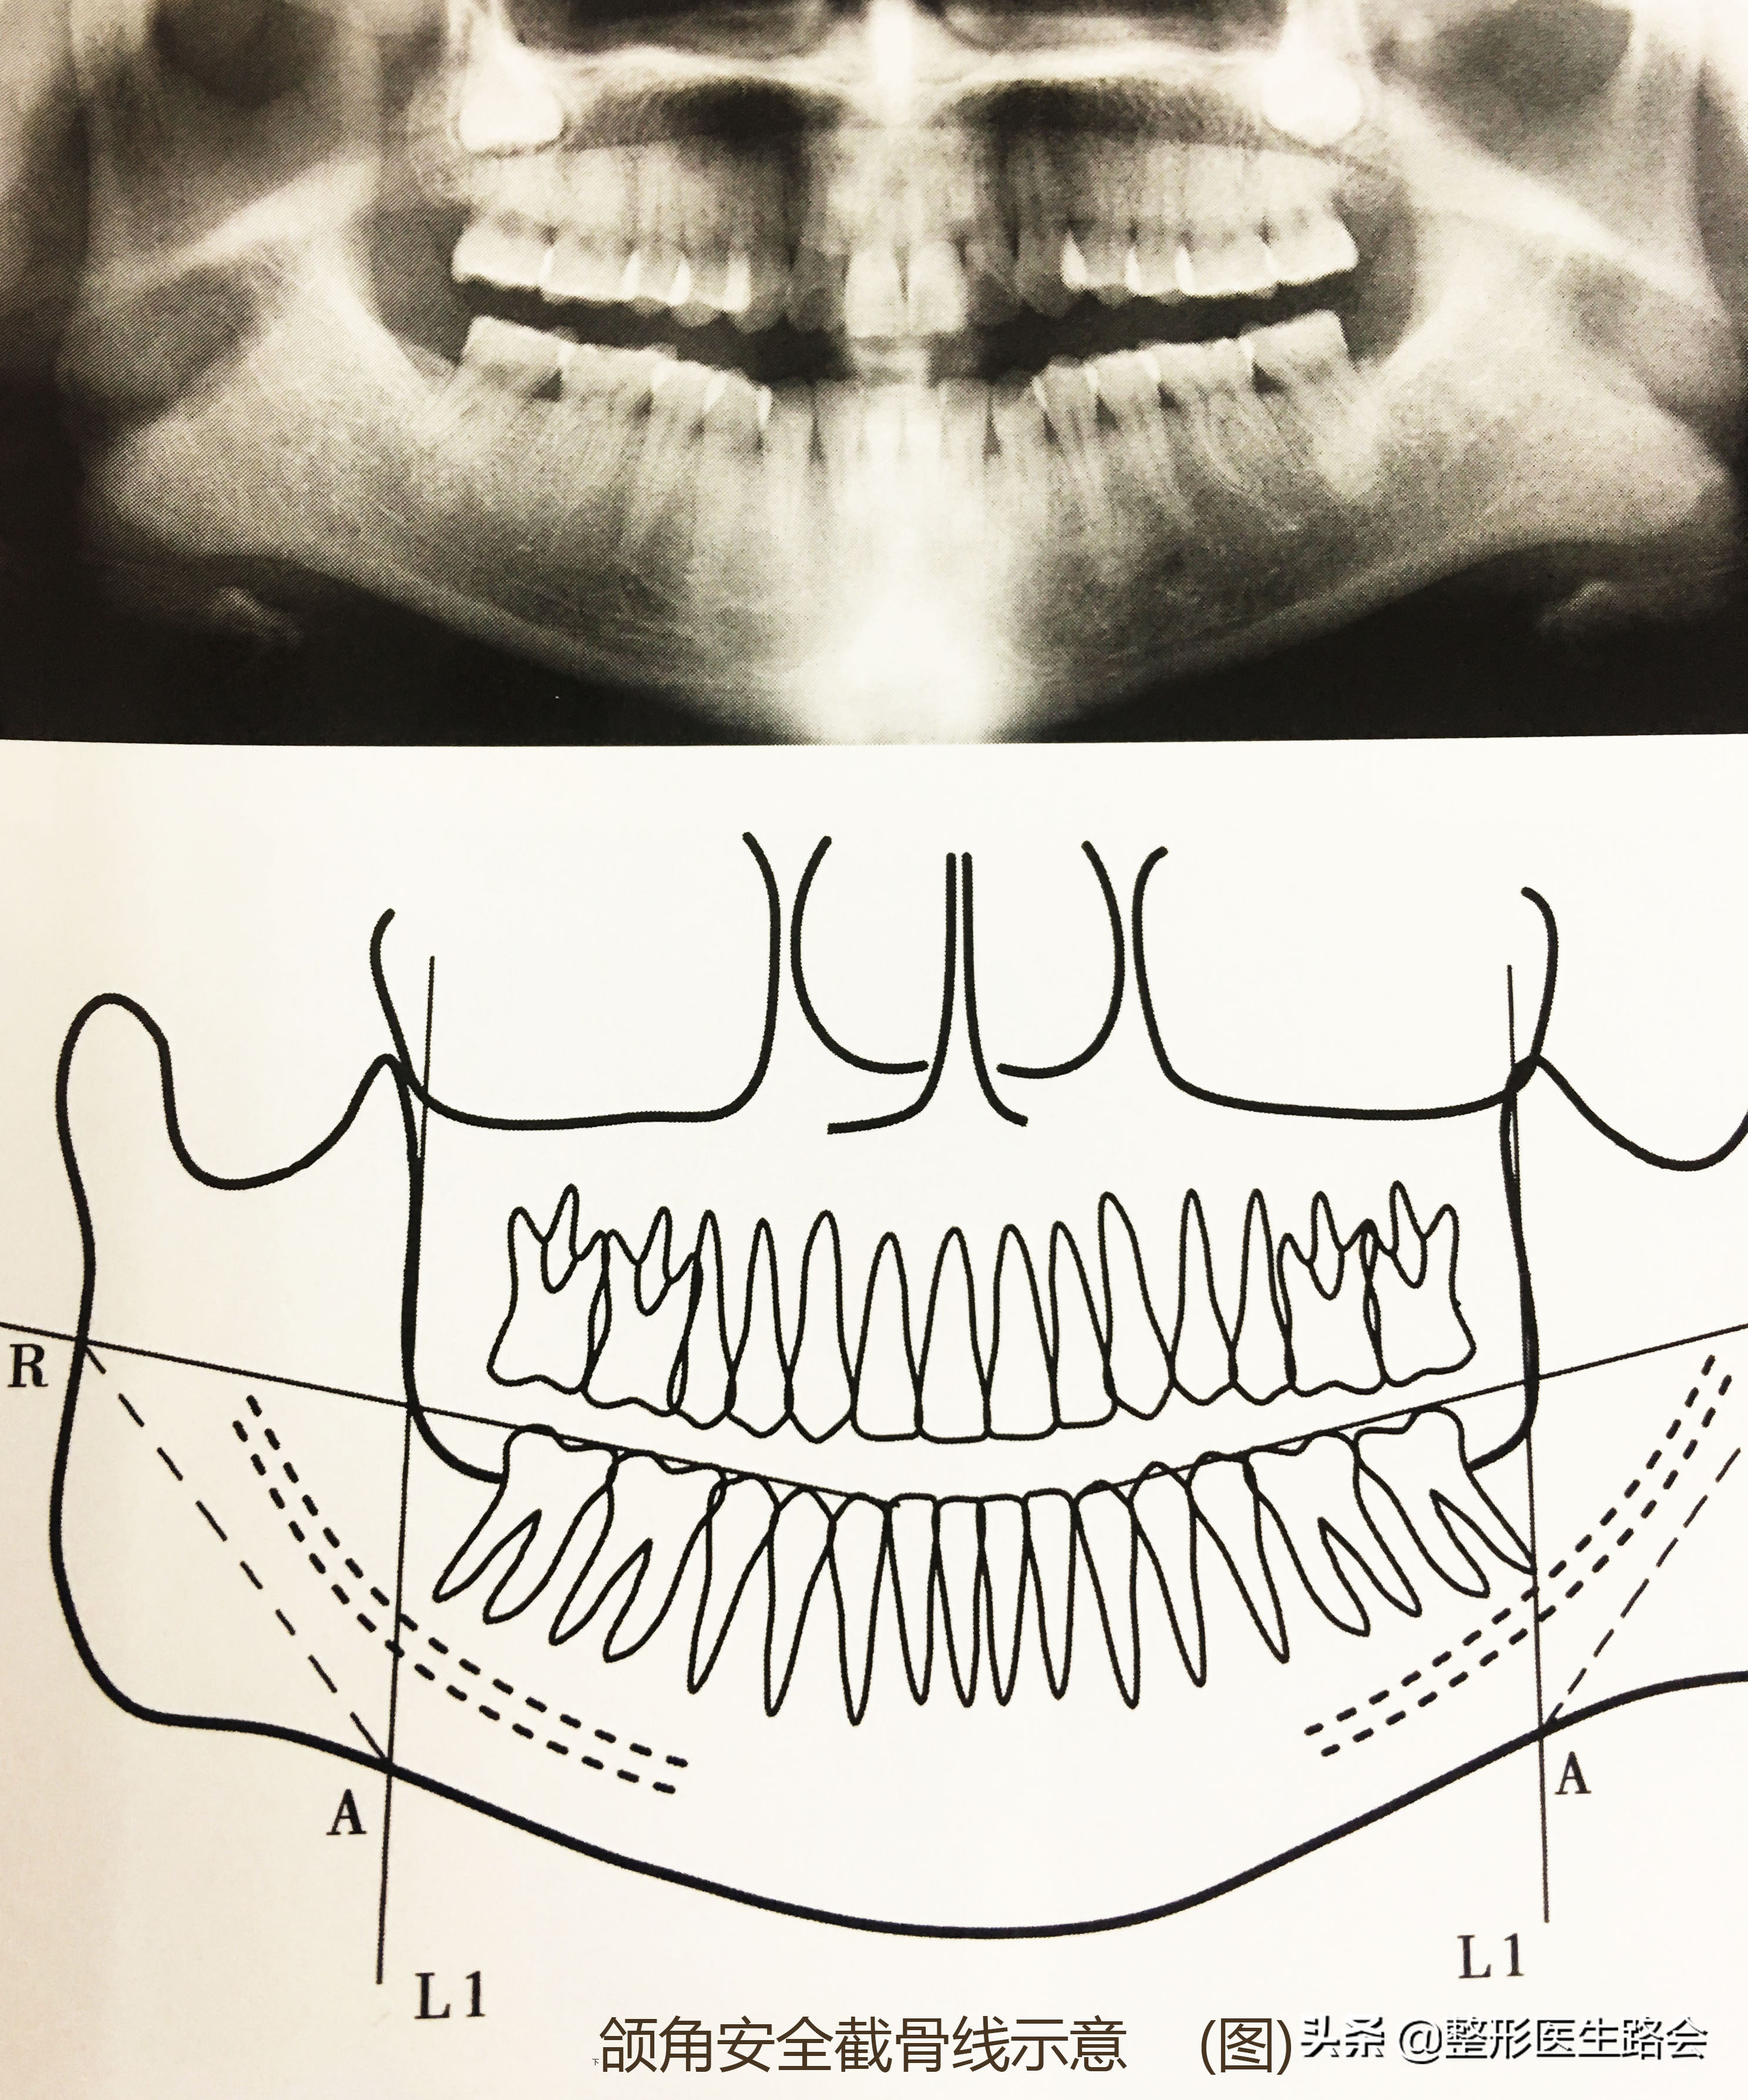

2. 根據(jù)設(shè)計(jì)的截骨量,畫(huà)出截骨線;

截骨線

補(bǔ)充:應(yīng)該在距離下齒槽神經(jīng)管下方5mm以上。向上,可能會(huì)造成手術(shù)器具對(duì)下齒槽神經(jīng)產(chǎn)生損傷,過(guò)遠(yuǎn),則可能遠(yuǎn)遠(yuǎn)達(dá)不到手術(shù)果)